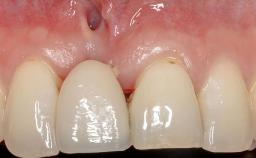

A 30-year-old woman was referred by her general dentist for evaluation of an esthetic complication related to previous implant treatment for congenitally missing maxillary lateral incisors. The patient’s chief complaint was the inadequate esthetic appearance of her smile. The case demonstrates the use of a combined approach to achieve optimal results. Two different flap designs - a tunnel technique and a coronally advanced flap - are employed based on the surgical objectives for the affected site.

Soft Tissue Anatomy Intact Defective